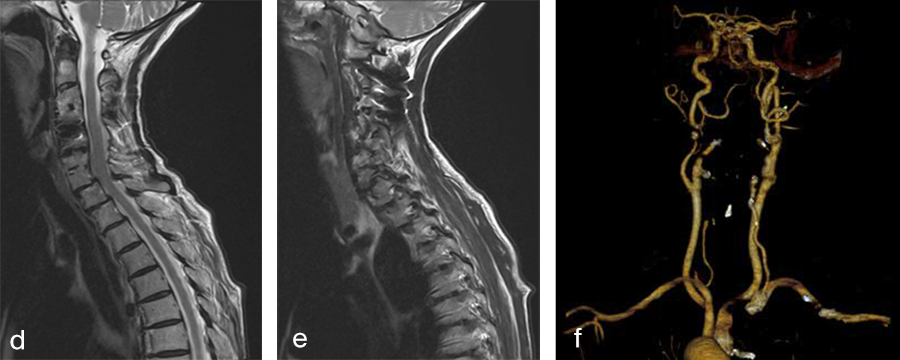

Her preoperative radiographic evaluation comprised x-rays, functional x-rays, computed tomographic, and magnetic resonance imaging scans (Fig 4) and demonstrated:

- A fusion of the motion segments C2/3/4 and C6/7

- A moderate implant loosening of the posterior C2 screw on the right side

- An afunctional disc prosthesis at the level C4/C5 with significant heterotopic ossifications (grade III) accompanied by a facet joint osteoarthritis in this motion segment

- A nonunion at the level C5/C6 with residual mobility in this motion segment

- A highly mobile degenerative spondylolisthesis at the level C7/Th1 with bilateral neuroforaminal stenosis

Preoperative imaging (Fig 4a-f), showing:

- C2-C4 posterior instrumentation and fusion.

- Anterior fusion after Anterior Cervical Decompression and Fusion (ACDF) C3/4 and C6/7.

- Status after total disc replacement of C4/5 with heterotopic ossifications.

- Nonunion C5/6 after ACDF C5/6.

- Spondylolisthesis C7/Th1 with neuroforaminal stenosis on both sides.

-  A normal cervical angiogram (cave: artefacts).